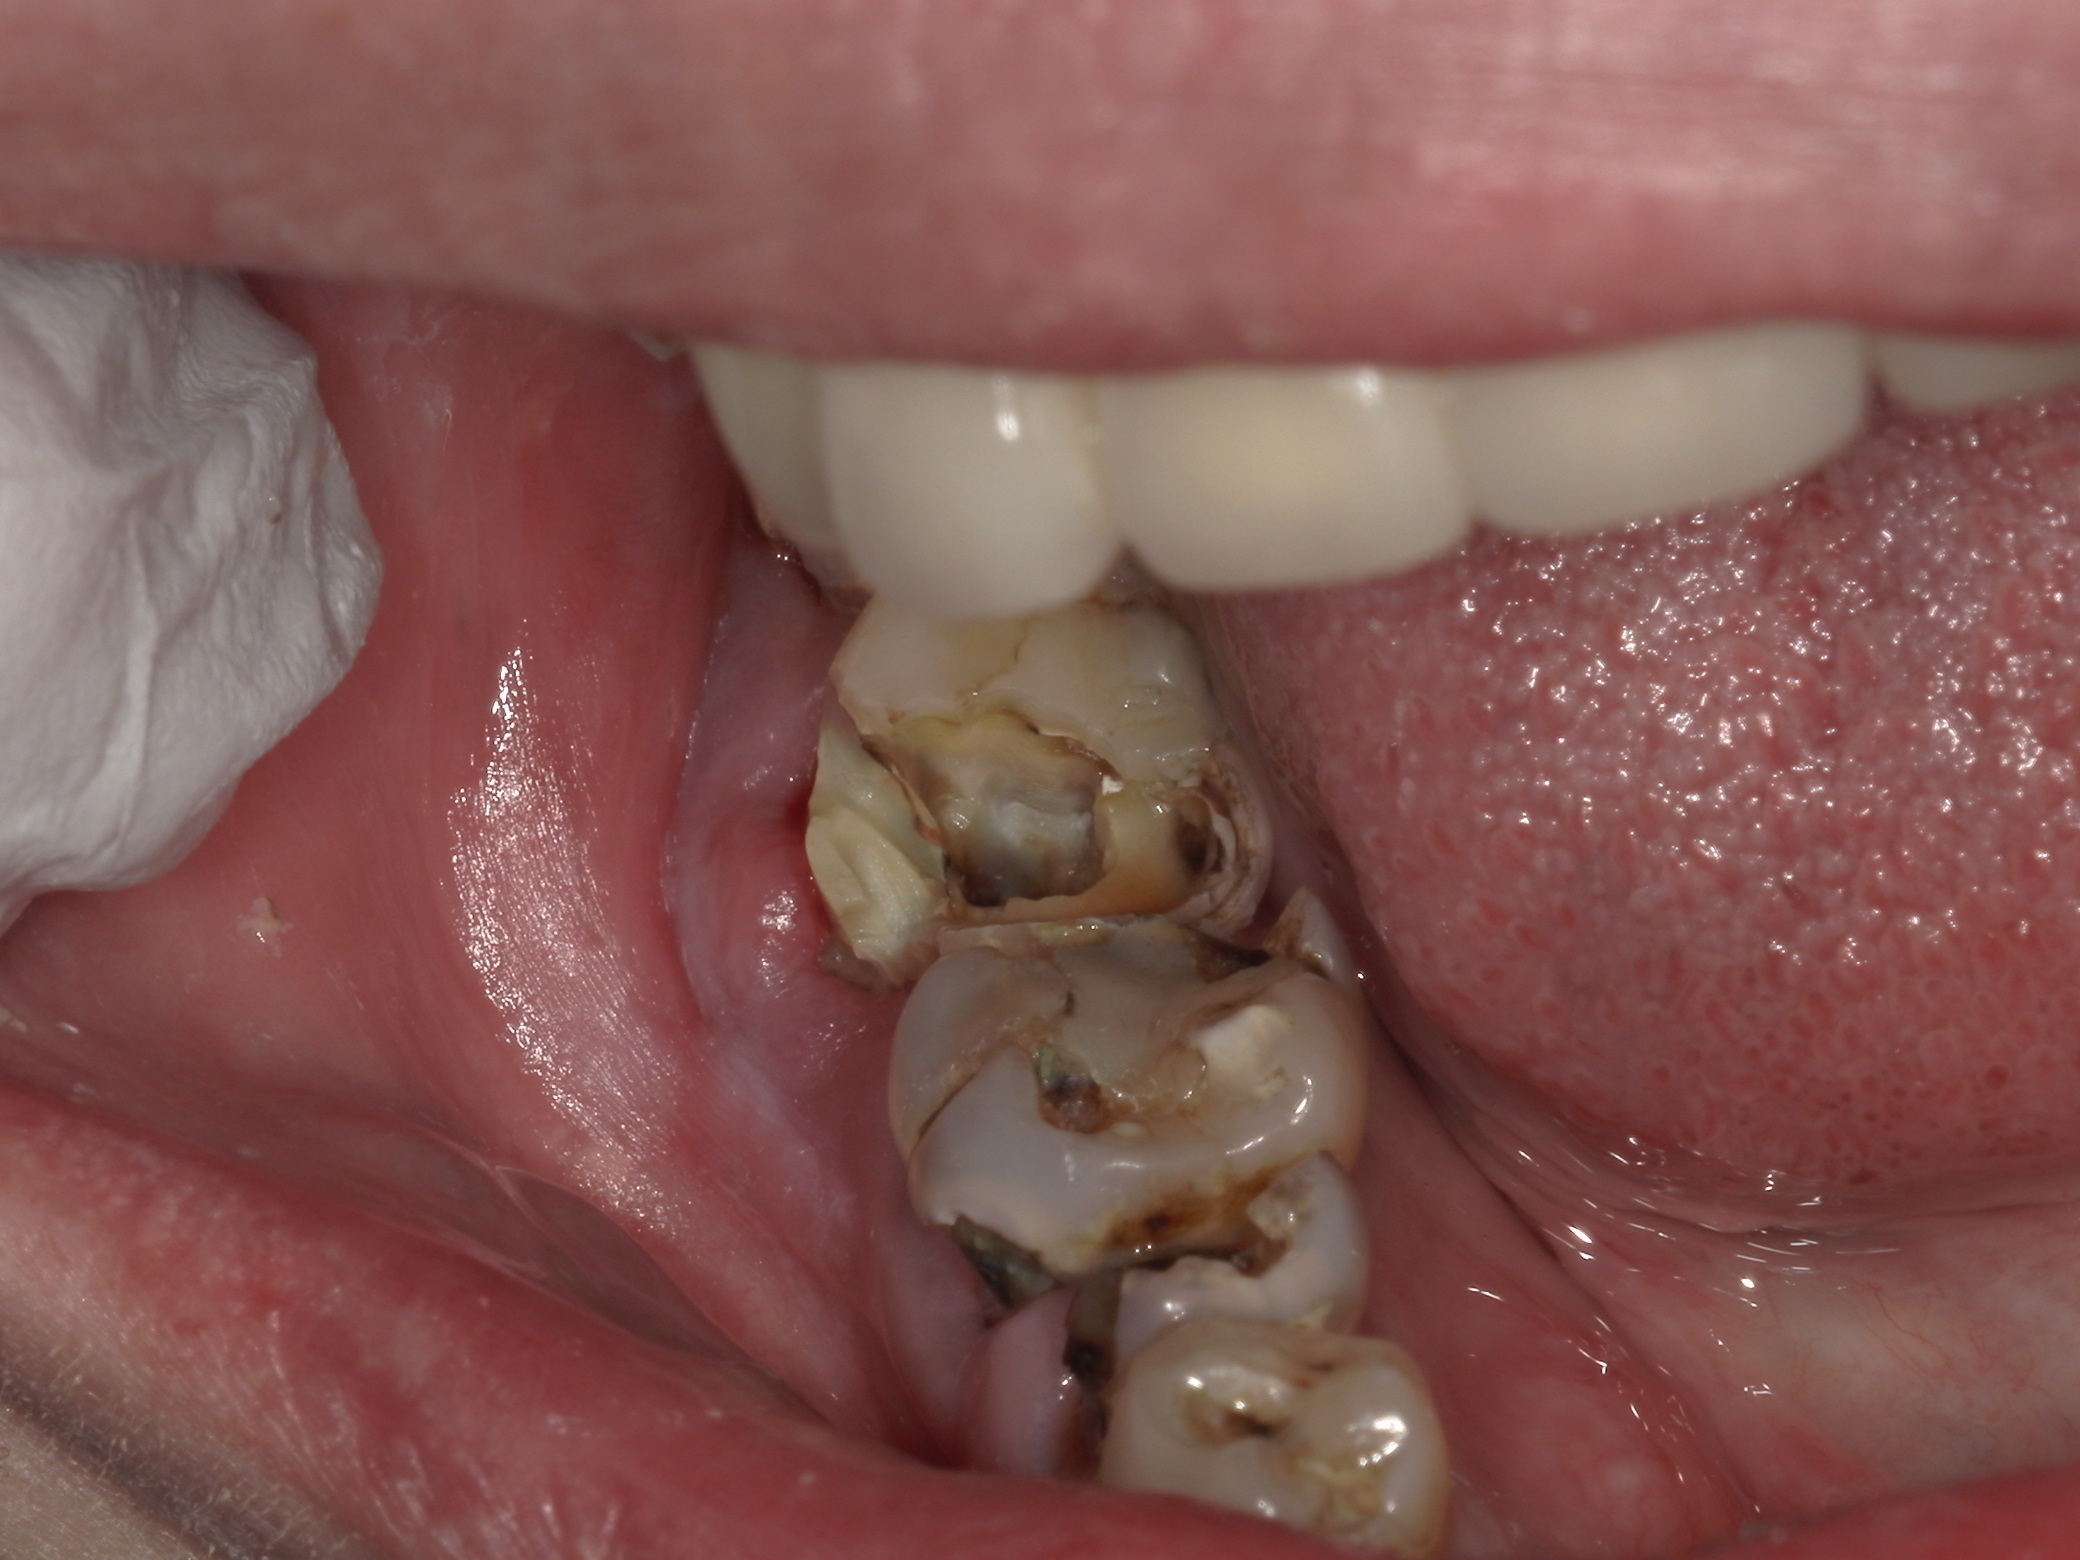

ドックベストセメント治療の問題点

先日3例目のドックベストセメント治療を受けた酸蝕歯の患者さんが何回通院しても治らないということ...

ドックベストセメント治療の失敗

先日2例目のドックベストセメント治療でトラブルになった患者さんが来院された。 写真の右下7番は...

ドックベストセメント治療の被害

最近、ドックベストセメントによる治療のトラブル例が増えています。 写真はドッグベストセメント治...